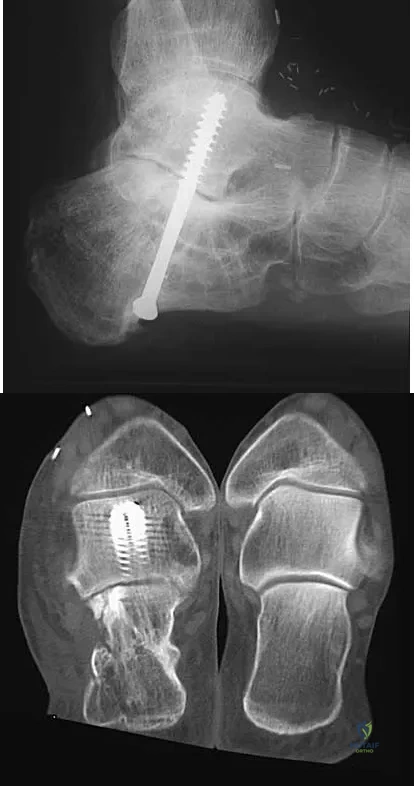

Question 49

A 45-year-old man has persistent hindfoot pain that is aggravated by weight-bearing activities. History reveals that he sustained a calcaneus fracture 2 years ago, and he underwent a subtalar fusion 1 year ago. Examination reveals tenderness in the sinus tarsi and across the transverse tarsal joint. A plain radiograph and a CT scan are shown in Figures 24a and 24b. A technetium Tc 99m bone scan reveals uptake at the subtalar joint and at the transverse tarsal joints. Management should now consist of

Explanation